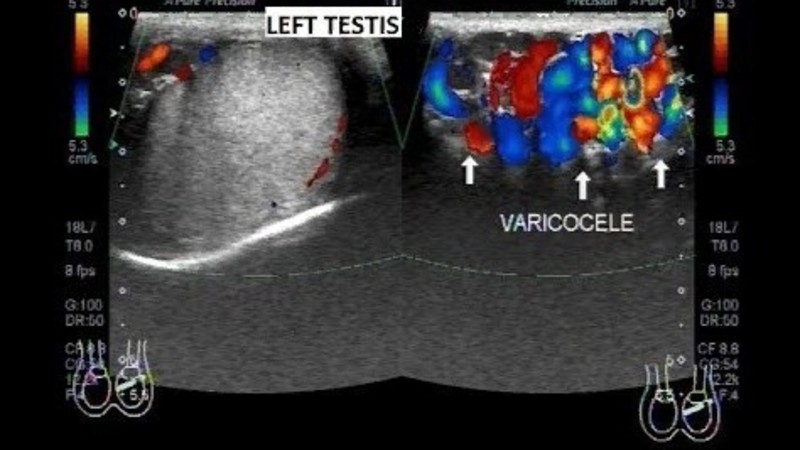

После операции при варикоцеле может ли быть бесплодие - фото презентация